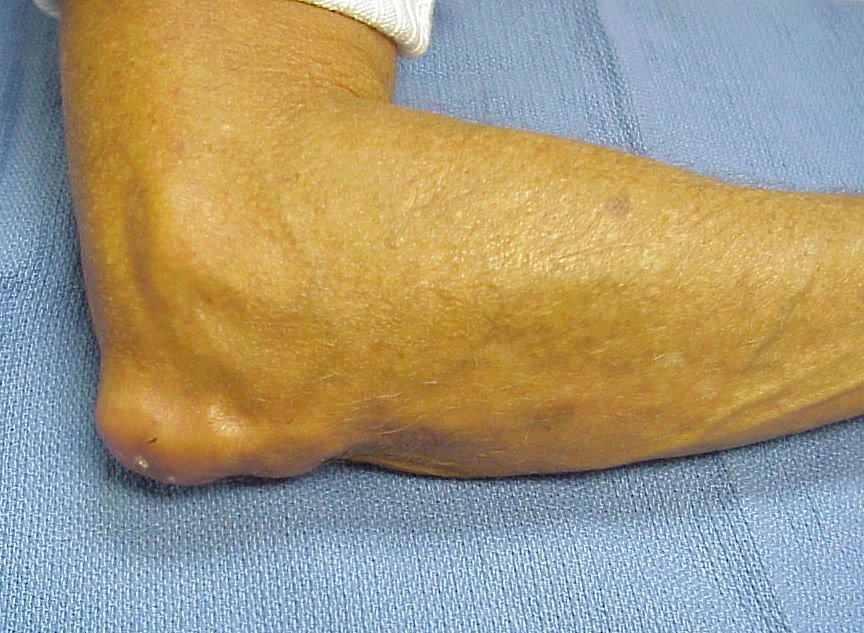

Clinical Example: CREST syndrome with scleroderma, telangiectasias and subcutaneous calcification

Scleroderma is a systemic disease, but commonly affects the hands in several ways. Finger stiffness is typical. Scleroderma may be associated with other syndromes, and a common combination is Calcinosis, Raynaud's, Esophageal motility disorders, Scleroderma and Telangiectasias - CREST syndrome. In this syndrome, the hands are affected by calcinosis, Raynaud's and scleroderma. Skin ulcerations may arise from Raynaud's related peripheral vascular insufficiency (fingertips), from scleroderma related skin tightness (extensor surfaces of the proximal interphalangeal or metacarpophalangeal joints), or from extrusion of subcutaneous calcium formations (any location).

Subcutaneous calcification of the extensor surface of the elbow is common, and a common site for spontaneous drainage and infection.